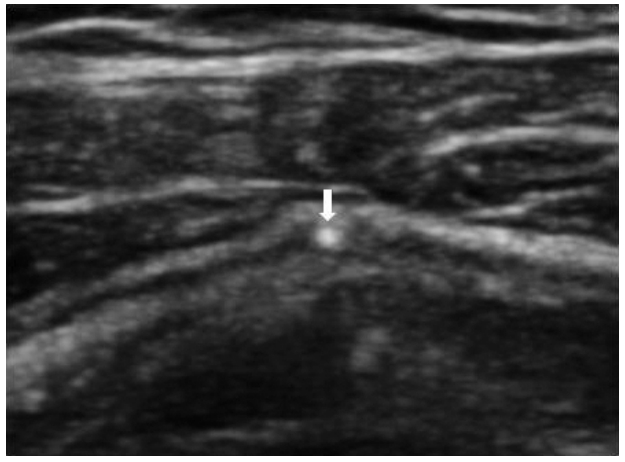

중족지(metatarsophalangeal)관절과 같이 작고 표재성인 관절은 in-plane 접근이 사실상 어렵기 때문에 out of plane 접근법으로 탐촉자의 중심에서 직각으로 바늘을 진입시켜 주사한다(Fig. 11). 중족지관절의 삼출액을 흡인하여 편광현미경 검사를 하고자 할 때, 초음파 유도가 매우 유용하며, 삼출액의 양이 많지 않은 경우엔 초음파 유도 하에 생리식염수를 관절내에 주입한 후 검체를 얻을 수도 있다.